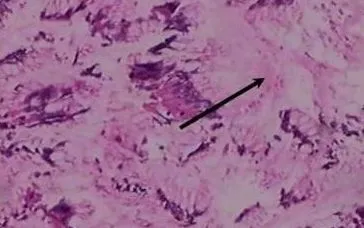

Bất ngờ xuất hiện khi phân tích mô bệnh học: dưới kính hiển vi, bác sĩ phát hiện giun lươn ký sinh trong niêm mạc ruột non, hoàn toàn không có tế bào ung thư như nghi ngờ ban đầu.

Giải phẫu bệnh không chỉ nhằm phát hiện ung thư mà còn giúp nhận diện các nguyên nhân hiếm gặp như ký sinh trùng. Quan sát kỹ mẫu mô giúp tránh chẩn đoán nhầm, hạn chế can thiệp không cần thiết và mở ra hướng điều trị đúng thuốc, kịp thời.